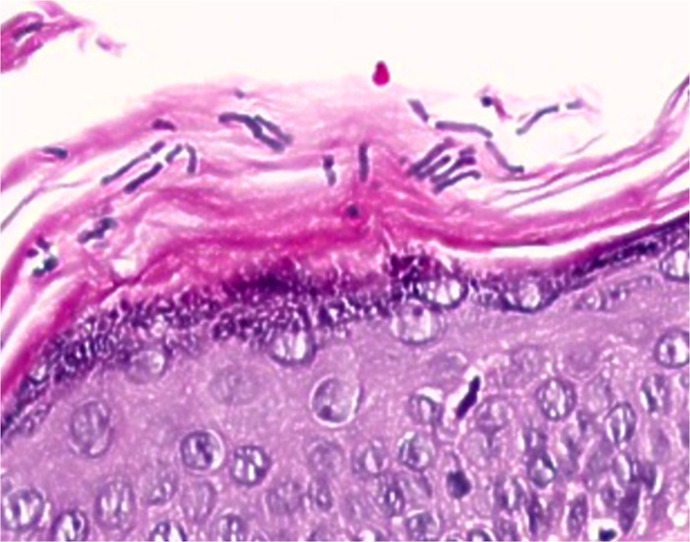

Case presentation: Here, we present a case of a 92-year-old female without associated chronic diseases, who lived alone in urban apartment and developed kerion in addition to having chronic untreated toenail onychomycosis and tinea pedis. Using PCR, we confirmed Trichophyton rubrum as the causative pathogen of toenail onychomycosis and kerion, suspecting autoinoculation pattern of transmission of dermatophytes from feet to the scalp. With the literature review, we discovered sporadic case reports, linking toenail onychomycosis caused by T. rubrum to development of kerion and kerion-like lesions in adult patients.